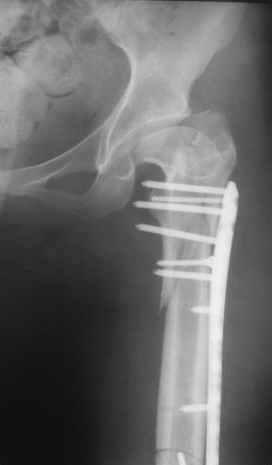

Пациентка 23 лет, доставлена в клинику с Диагнозом: Закрытый сегментарный оскольчатый перелом левой бедренной кости в верхней и средней трети. Травма в результате ДТП 10.03.2006г. Из анамнеза у пациентки диспластический левосторонний коксартроз, S-образный сколиоз 2ст. В 1999г в Кургане выполнялась остеотомия бедра в нижней трети и коррекция укорочения конечности на 3 см (рентгенограммы бедра и таза до травмы в приложении). До получения травмы пациентка ходила без боли с полной нагрузкой на левую ногу. Учитывая дисплазию левого ТБС, пациентке, вероятно, предстоит операция тотального эндопротезирования лев ТБС, что требует анатомичного восстановления проксимальногоотдела бедра. Рассматриваются следующие вариант остеосинтеза:1) Экстракортикальный остеосинтез проксимального и дистального перелома пластиной с угловой стабильностью типа LISS( г Рыбинск); 2) Ретроградный интрамедуллярный блокированный остеосинтез дистального перелома и накостный синтез проксимального пластиной с угловойстабильностью; 3) Остеосинтез бедра в аппарате внешней фиксации с фиксацией таза и возможной открытой адаптацией фрагментов. Хотелось бы узнать Ваше мнение. С уважением Украинский Евгений, г.Краснодар, ККБ N1, ТОО N3.

Судя по снимкам до перелома, большой вертел располагался высоковато. Может, подумать о том, чтобы при остеосинтезе его переместить дистальнее и/или латеральнее? Что скажут коллеги, активно занимающиеся эндопротезированием?

Не во всех случаях, особенно у молодых!, при дисплазии ТБС требуется эндопротезирование. По представленным снимкам четко видны хорошо сохраненный тазобедренный сустав и тем более больная до травмы не имела симптомов диспластического сустава. В будущем при появлении симптомов, можно попытаться сделать реконструктивную работу по сохранению сустава: ПАО с удлинением шейки (аналогичные случаи были

Учитывая, что в проксимальная часть бедра в скором будущем будет нуждаться в больших оперативных вмешательствах, я бы старался сохранить проксимальное кровообращение бедра и поэтому считаю антеградное штифтование неприемлемым методом для данного случая.

При антеградном методе, в зависимости от место введения штифта, особенно если введение штифта происходит через piriformis fossa, имеется большая вероятность повреждения medial artery circumflex

(медиальной огибающей артерии). Менее опасным считается введение через верхушку большого вертела. Кстати, новые снимки с дистракцией